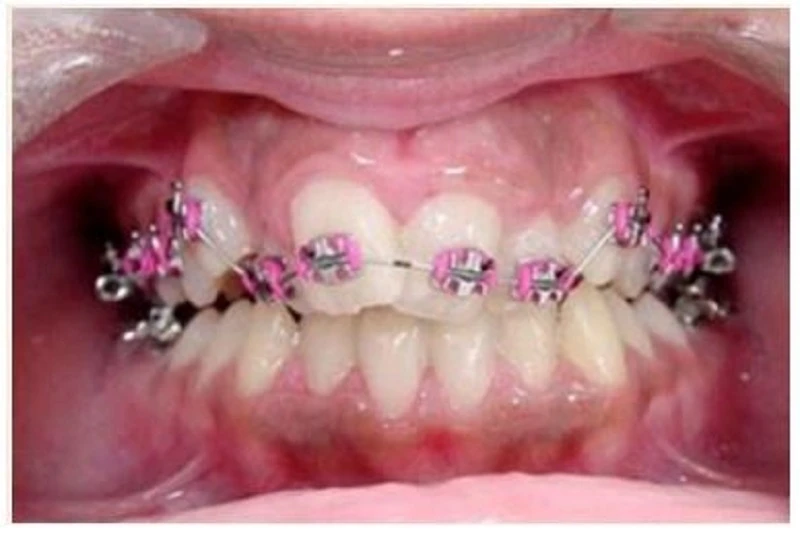

Sau khi gắn band và mắc cài, dây cung sơ khởi sẽ được buộc vào mắc cài. Bất cứ sự chuyển dạng nào của dây cung này cũng gây ra lực đặt lên răng, hoạt hóa cơ chế sinh học của di chuyển răng. Nếu chỉ có mắc cài và band thì không thể di chuyển răng được. Răng di chuyển để đáp ứng với lực áp dụng, và dây cung là phương pháp tiện dụng để áp dụng lực này.

Dây cung sơ khởi sẽ luôn luôn là dây cung Niti. Các dây này có TRÍ NHỚ để khi dây cung bị bóp méo khỏi hình dạng ban đầu, nó sẽ muốn quay lại hình dạng nguyên thủy của mình. Dây cung sẽ phải vặn xoắn khi buộc chúng vào mắc cài của các răng lệch lạc, tạo nên lực trên dây chằng nha chu vì dây cung muốn trở lại hình dạng ban đầu. Lực xoắn vặn, hợp kim làm dây cung và nhiệt hóa dây cung, và kích thước dây cung sẽ xác định mức độ lực đặt lên răng.

Mục tiêu của giai đoạn làm thẳng là để dây cung nằm thụ động trong khe mắc cài. Mắc cài đặt trên răng ở vị trí tiêu chuẩn, và sau đó buộc dây cung Niti cho đến khi nó nằm THỤ ĐỘNG trong khe mắc cài. Khi dây đã nằm ở vị trí thụ động tại mỗi mắc cài thì có thể buộc dây cung vào khe mắc cài bằng chun tại chỗ. Nếu dây cung chưa nằm thụ động (ví dụ: bạn phải ấn dây vào khe mắc cài và khi giải phóng áp lực đó thì dây có thể bị bung ra), thì cần buộc bằng dây thép (ligature). Ligature thép sẽ giữ dây cung niti trong giai đoạn chưa thụ động này cho đến khi có thể buộc dây vào mắc cài hoàn toàn.